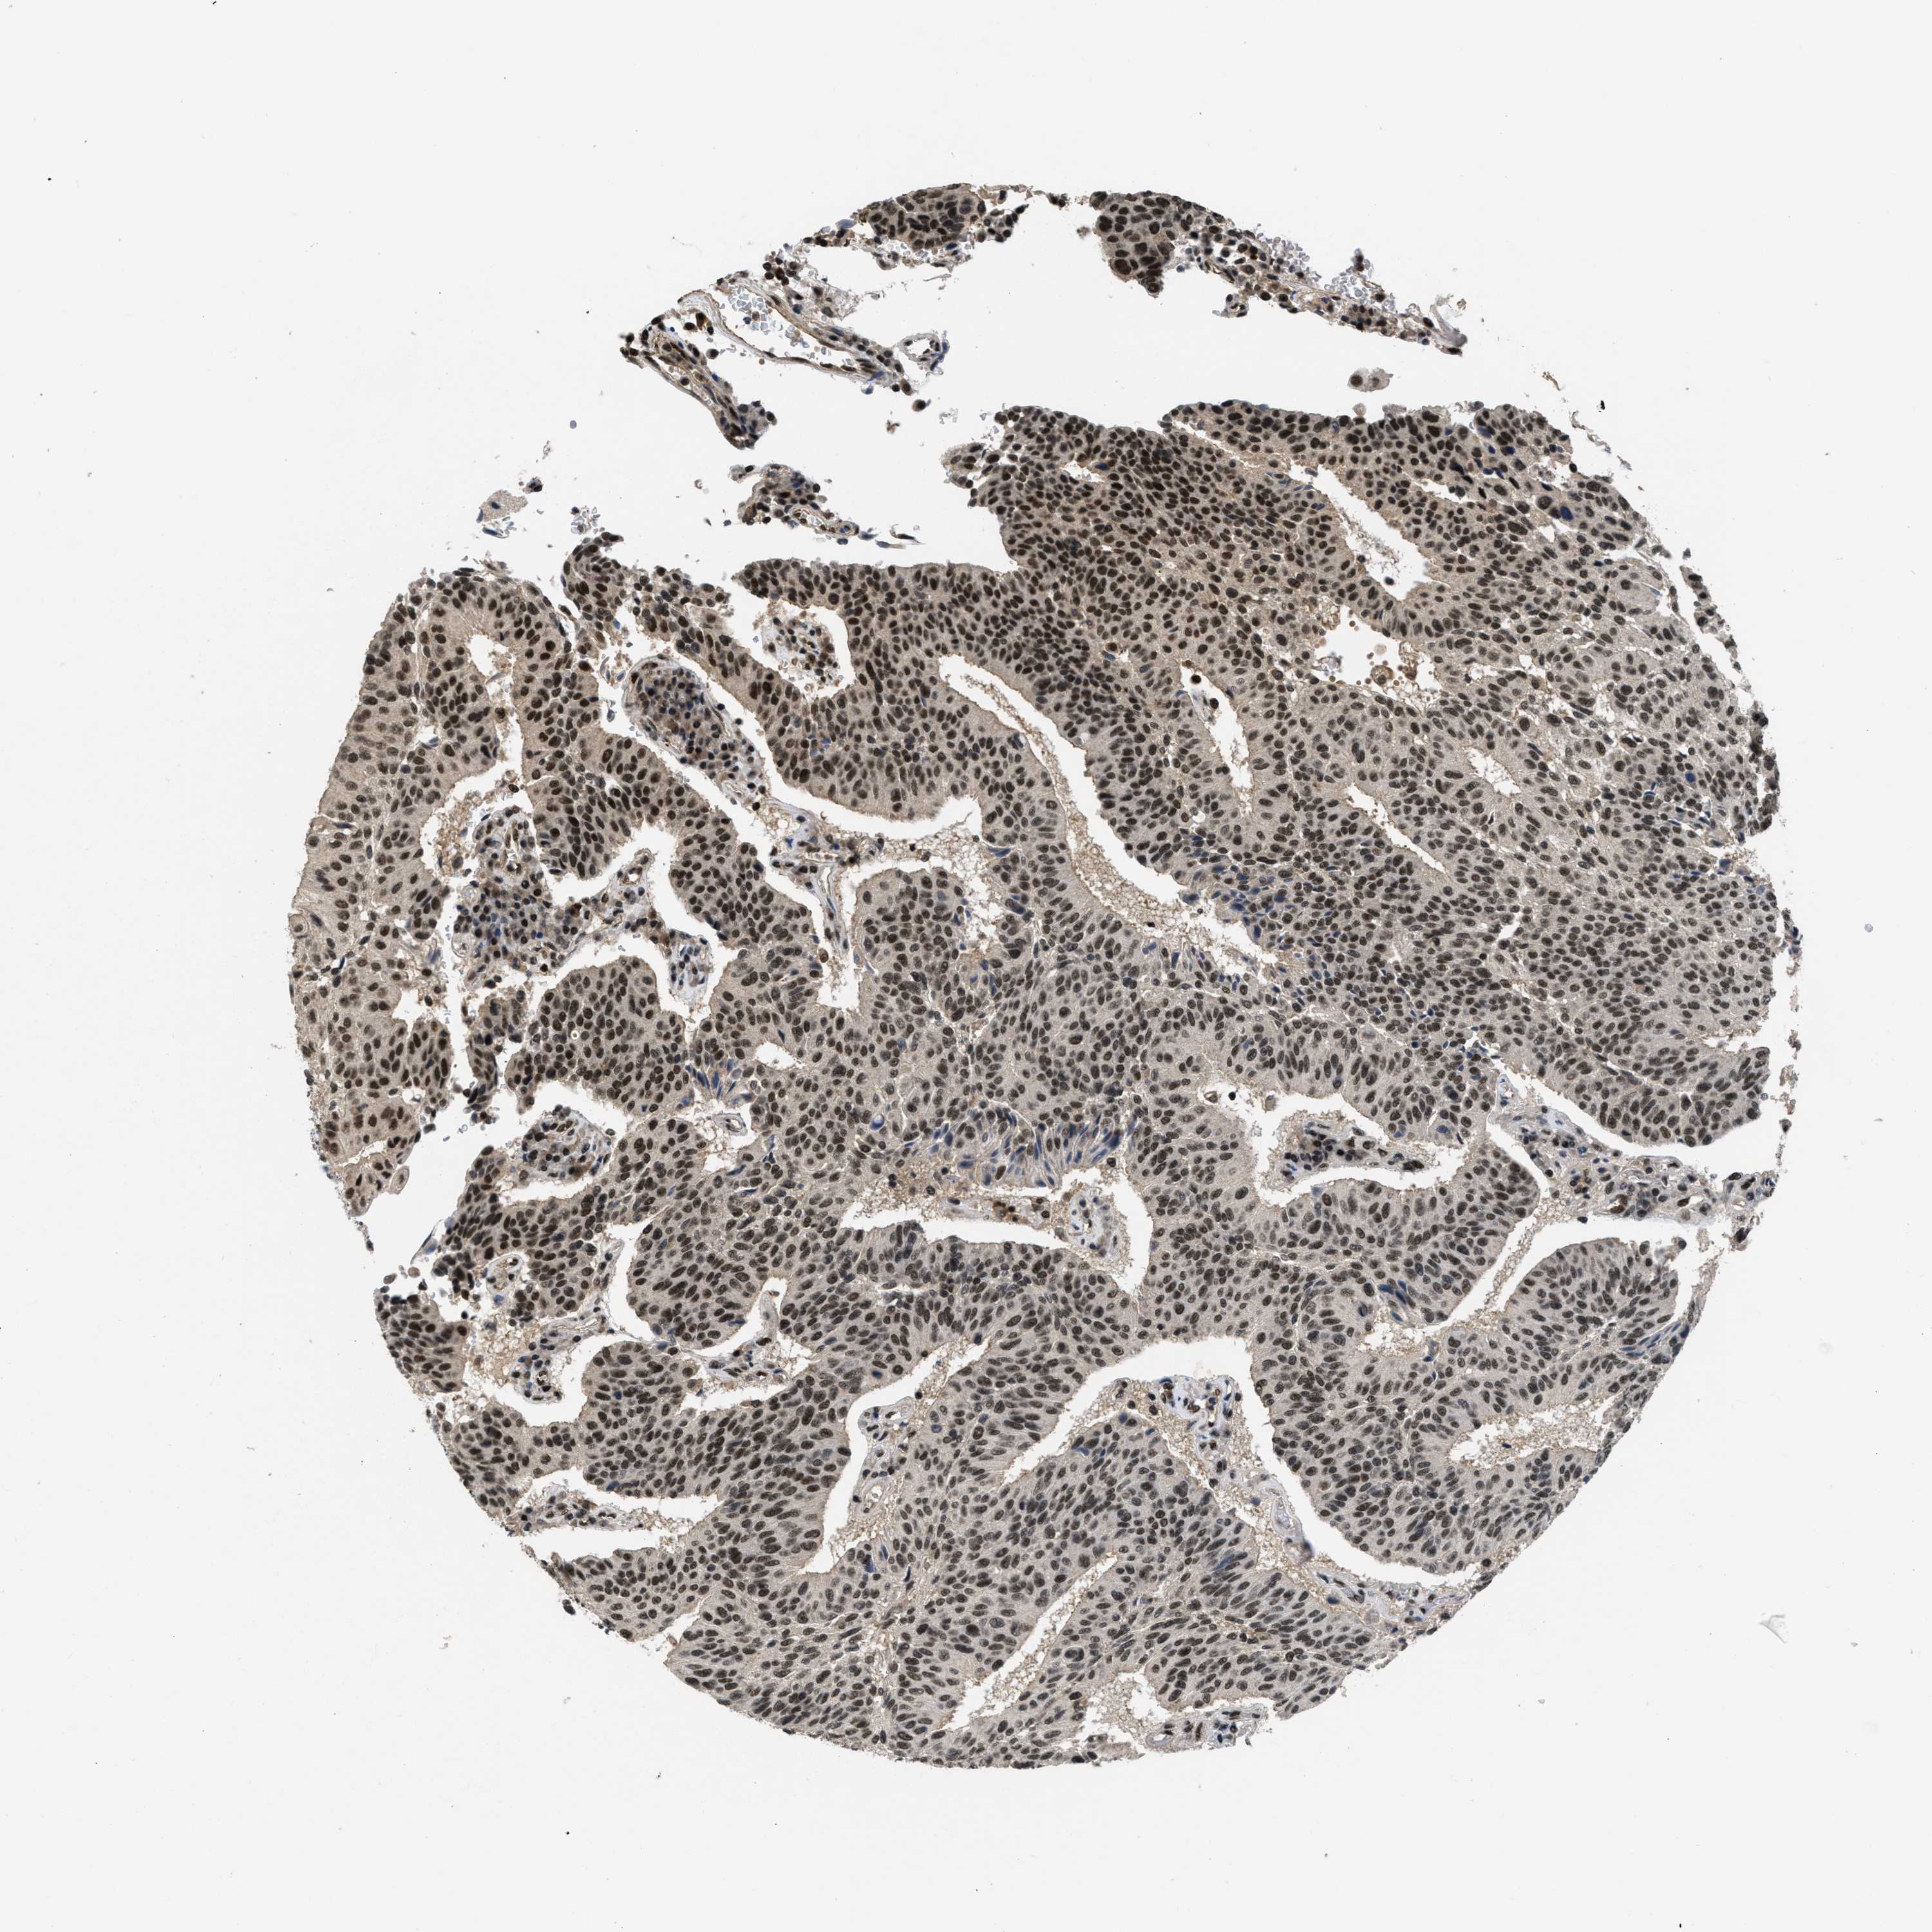

UROTHELIAL CANCER - Protein expressioni

A mouse-over function shows sample information and annotation data. Click on an image to view it in a full screen mode. Samples can be filtered based on level of antibody staining by selecting one or several of the following categories: high, medium, low and not detected. The assay and annotation is described here.

Antibody stainingi

Antibody staining in the annotated cell types in the current human tissue is reported as not detected, low, medium, or high, based on conventional immunohistochemistry profiling in selected tissues. This score is based on the combination of the staining intensity and fraction of stained cells.

Each image is clickable and will lead to virtual microscopy that enables deeper exploration of all samples and also displays staining intensity scores, fraction scores and subcellular localization as well as patient and tissue information for each sample.

Antibody HPA011880

Antibody CAB017786

Urothelial carcinoma, Low grade

Urothelial carcinoma, High grade